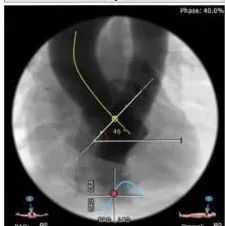

在放射科,超声科和麻醉科的通力协作下,顺利完成了术前准备,术者团队在术中谨慎建立轨道,根据主动脉根部造影的结果选择合适的跨瓣体位。

主动脉根部造影